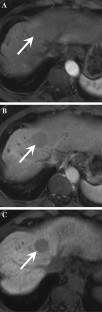

Fig. 4